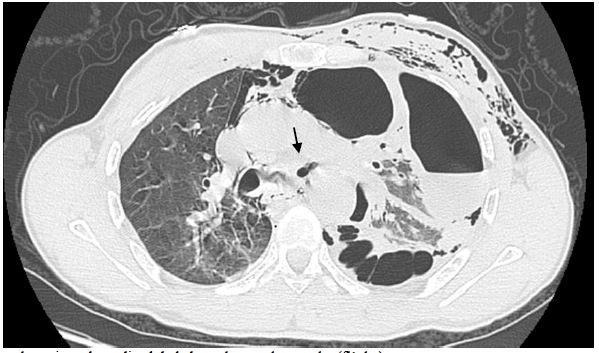

Mr T.A âgé de 47 ans, tabagique chronique, a été victime le 22 janvier 2011 d’un traumatisme thoracique fermé violent secondaire à un accident de travail à Errachidia, ville situé à 364 km de Fès. Il a été écrasé contre un mur par un camion benne transportant du sable, faisant marche arrière, avec un point d’impact principalement thoracique sans notion de perte de connaissance, ni d’hémoptysie. L’examen à son admission au service d’accueil des urgences, trouvait un patient conscient, polypneique à 20 cycles /min, la fréquence cardiaque était à 90 batt/min et la pression artérielle à 130/80 mmHg. L’examen du thorax, trouve des lésions ecchymotiques avec des douleurs à la palpation des côtes et un emphysème sous cutané. Les pouls périphériques étaient symétriques. L’auscultation pulmonaire trouvait une diminution du murmure vésiculaire du côté gauche. Le reste de l’examen était sans particularité. La radiographie du thorax a montré l’aspect d’un pneumothorax gauche cloisonné. Après la mise en condition, le patient est transféré aux urgences du CHU de Fès. Un scanner thoracique réalisé en urgence, a mis en évidence un pneumothorax gauche cloisonné, une contusion pulmonaire, des fractures costales gauches (du 3ème à la 6 ème côte), un emphysème sous-cutané, un pneumomédiastin et une rupture de la bronche souche gauche [fig1,2].